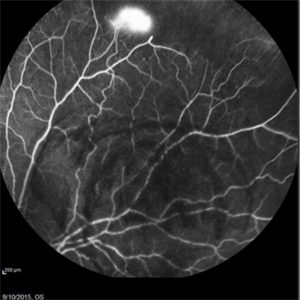

Angiography showed normal vessels posteriorly but severe capillary drop out throughout the periphery OU with scattered severe neovascularization at the edge of the capillary drop out peripherally.

Sickle Cell Retinopathy Sickle Cell RetinopathySep 13 2015 by Thomas A. Ciulla, MD, MBA, FASRS Angiography showed normal vessels posteriorly but severe capillary drop out throughout the periphery OU with scattered severe neovascularization at the edge of the capillary drop out peripherally. Photographer: Thomas Steele Condition/keywords: peripheral retinal neovascularization, sea fan, sickle cell retinopathy